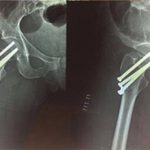

Zoe Schaffer-Jennett, 27, suffered a complicated femoral neck fracture in her hip that will leave her bedbound for months.

She is currently recovering from a four-hour long surgery during which three screws had to be placed in her leg to reattach her femoral head to the bone.

‘This was the most stressful situation for us as we wanted the best treatment for her even if we had to put ourselves in debt,’ he added. Pictured are X-Rays of the broken hip

She is currently recovering from a four-hour long surgery during which three screws had to be placed in her leg to reattach her femoral head to the bone